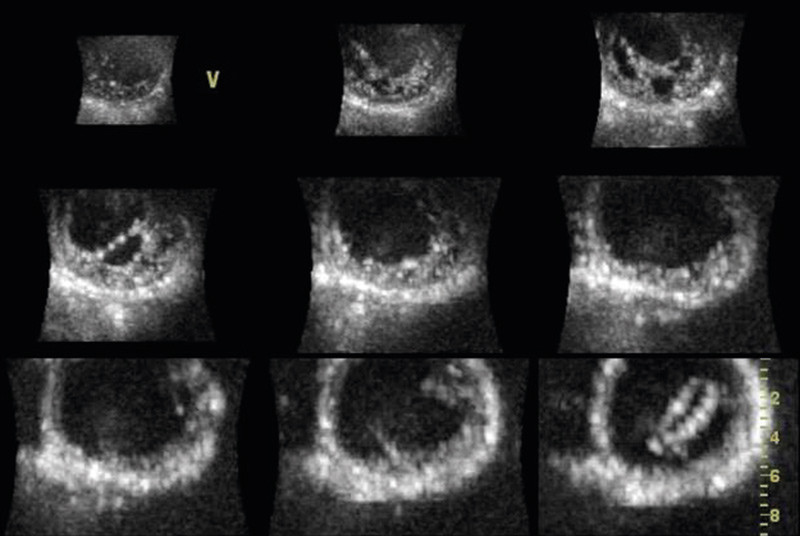

Using 3D echocardiography with full volume recording, the left ventricle can be represented as multiple short-axis images on the screen (Figure 4). In heart muscle diseases such as hypertrophic cardiomyopathy, a better overview can be obtained of where the hypertrophy is distributed. This is particularly useful with more apical variants, as they can be overlooked in routine echocardiography. Some rarer forms of cardiomyopathy, such as non-compaction cardiomyopathy, have characteristic features which can be reproduced easily with 3D echocardiography (Figure 5). However, the additional value of 3D echocardiography in various cardiomyopathies has not as yet been well documented.

Figure 4  Short-axis sections of left ventricle from full volume recording in a normal, healthy individual. At the top left…

Figure 4 Short-axis sections of left ventricle from full volume recording in a normal, healthy individual. At the top left are apical sections, at the bottom right basal sections. All the short-axis images can be reproduced in real time simultaneously. Regional contraction abnormalities can be detected with this technique.